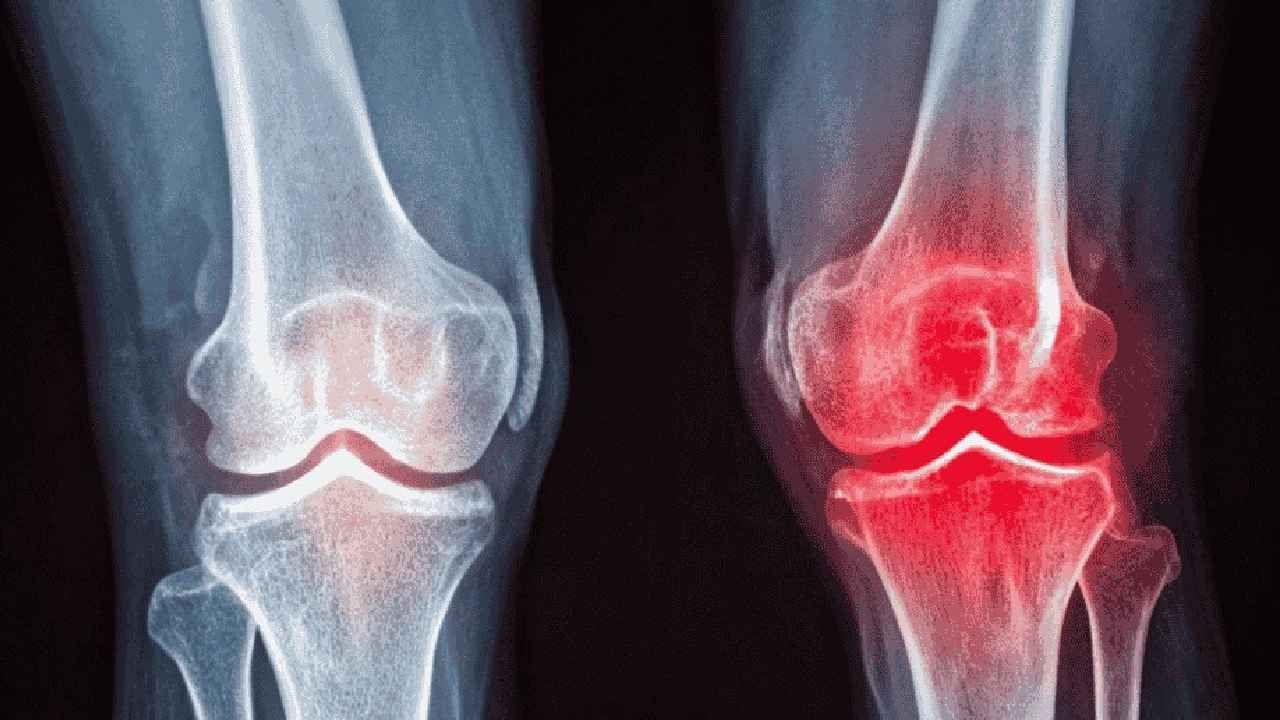

Tele1Czy operacja to ostatnia opcja w przypadku choroby zwyrodnieniowej stawu kolanowego? Nowoczesne terapie iniekcyjne i rola ćwiczeń fizycznych